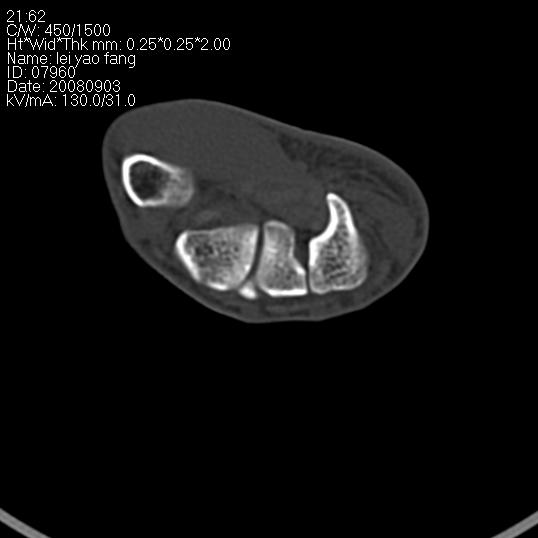

以下是引用杀毒软件在2008-9-4 17:41:00的发言:[br]考虑----舟骨囊肿